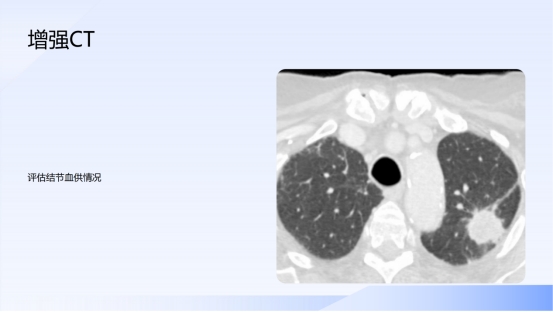

莫恐慌 重管理!肺结节科学认知十问十答

心胸血管外科    陈均